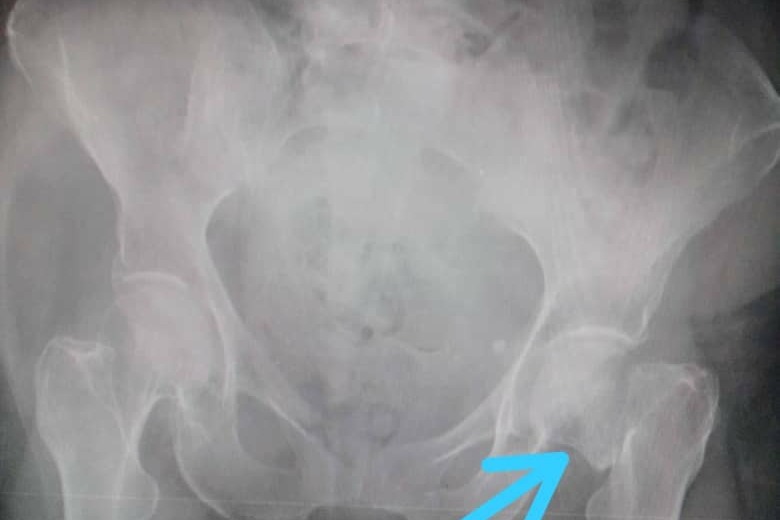

Beatriz del Carmen Fernandez De La Paz, 85 years young, fell and fractured her left femur on Sunday afternoon, December 26, 2020 as she arose from a nap. Her grandchildren rushed Beatriz to the Central Hospital of Maracay in Venezuela, the largest public hospital in the region, where she was denied care because the hospital lacks beds and patient care is backlogged for 2 months. Fortunately, Orthopedist, Dr. Carlos A. Hernandez C., of the private clinic Centro Medico, Maracay was able to see and evaluate her. Dr. Hernandez C. determined that Beatriz requires a prosthetic hip replacement surgery. Please see the attached documents with the doctor’s diagnosis, the x-rays, and the cost estimates for the prosthetic and procedure.

En la tarde del domingo 26 de diciembre del 2020 al levantarse de una siesta Beatriz del Carmen Fernández De La Paz, de 85 años de edad, sufrio una caida donde se fracturó el fémur del lado izquierdo de su cadera. Sus nietos la llevaron al Hospital Central de Maracay en Venezuela, el hospital público más grande de la región, donde se le negó la atención debido a que el hospital carece de camas y la atención de los pacientes está atrasada durante 2 meses. Afortunadamente, el ortopedista, Dr. Carlos A. Hernandez C., de la clínica privada Centro Médico, Maracay pudo atenderla y evaluarla. El Dr. Hernandez C. determinó que Beatriz requiere una cirugía de reemplazo de cadera prostética (Protesis de Cadera de Thompson) Adjuntos encontraran el diagnóstico del médico, las radiografías y las estimaciones de costos de la prótesis y el procedimiento a seguir.